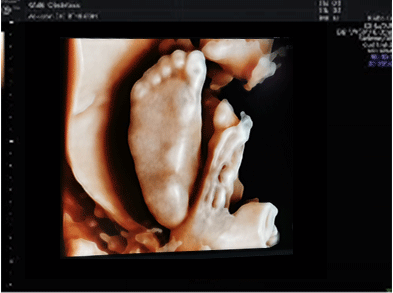

四維彩超成熟的煊光、煊影、煊流成像技術(shù),通過(guò)細(xì)致的多切面成像分析胎兒的解剖結(jié)構(gòu)及發(fā)育狀況能夠提供更多圖像數(shù)據(jù),可以更加清晰、完整的記錄胎兒宮內(nèi)的高清動(dòng)態(tài)。

獨(dú)有的表面模式、血管模式、組織血管透明模式等智能診斷模式,對(duì)胎兒的體表、內(nèi)臟、血管、骨骼等九大核心部位獨(dú)立成像,彌補(bǔ)傳統(tǒng)系統(tǒng)、四維彩超在檢測(cè)范疇及精準(zhǔn)度的局限性。